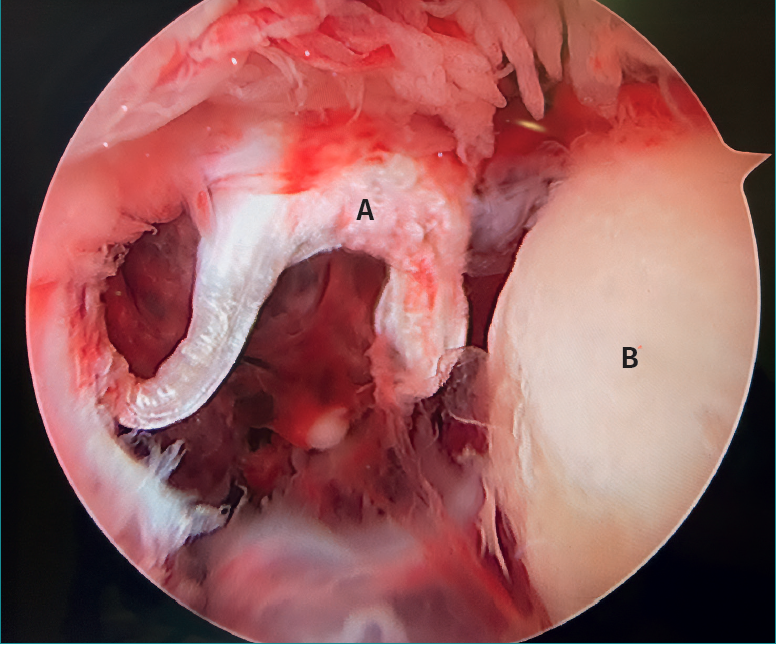

- The letter pi on the ankle